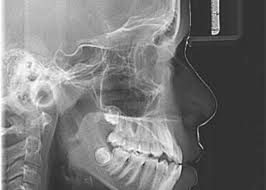

Mengapa Sebelum Pasang Behel Harus Foto Panoramik dan Cephalometri?

Anggelia Gita Tiyananda A.Md.Kes.(Rad)

Halo, Sobat Jo! 👋 Sebelum memasang behel, dokter gigi biasanya akan menyarankan untuk melakuka...

Rontgen Cephalometry

Biaya Pemeriksaan Foto Rontgen Cephalometry

Rp 125.000